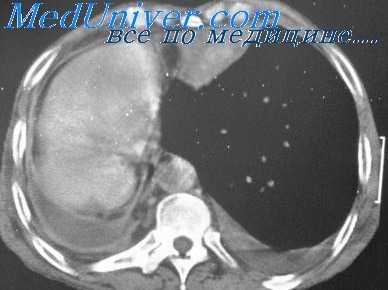

- тотальный - объем кровопотери свыше 2 л, рентгенологически характеризуется тотальным затемнением плевральной полости на стороне поражения.

Для постановки диагноза уточняются подробности истории заболевания, проводится физикальное, инструментальное и лабораторное обследование. При гемотораксе определяется отставание пораженной стороны грудной клетки при дыхании, притупление перкуторного звука над уровнем жидкости, ослабление дыхания и голосового дрожания. При рентгеноскопии и обзорной рентгенографии легких выявляется коллабирование легкого, наличие горизонтального уровня жидкости или сгустков в полости плевры, флотация (смещение) тени средостения в здоровую сторону.

- Рентгенография. При хилотораксе в нижних отделах грудной клетки обнаруживается горизонтальный уровень жидкости, затемнение гомогенное. При хилоперитонеуме наблюдается высокое стояние и ограничение подвижности диафрагмы.